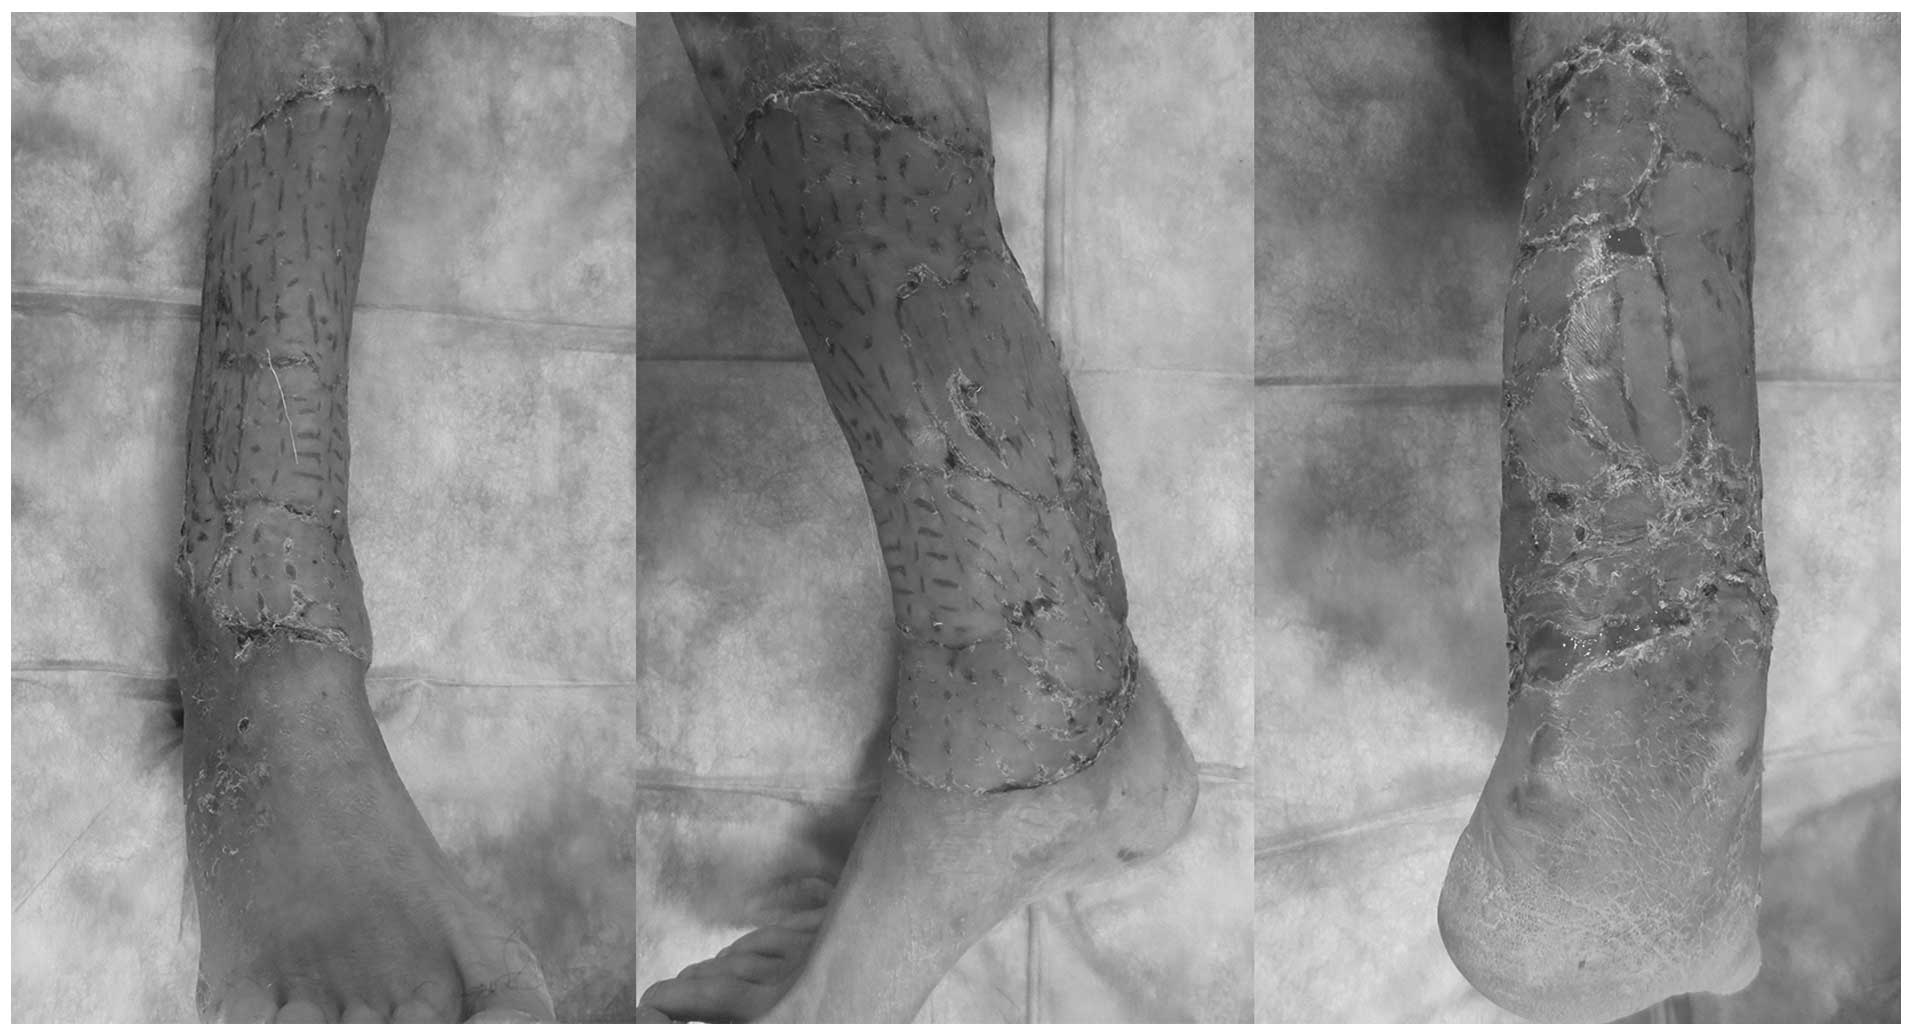

A 49-year-old male presented to Hunan Cancer Hospital and The Affiliated Cancer Hospital of Xiangya School of Medicine (Changsha, China) with a ulcerated skin lesion in the lower part of the right leg, for which amputation was suggested by doctors at other hospitals. The physical examination on admission revealed the presence of a ∼25×20-cm2 cutaneous cauliflower-shaped ulcerated lesion, with a specific odor and exudate, occupying one-third of the lower part of the leg (Fig. 1), with lymphadenopathy of the ipsilateral inguinal region. The preoperative pathological examination established the diagnosis of highly differentiated SCC and the bacteriological examination revealed infection by levofloxacin-sensitive Pseudomonas aeruginosa.

Prior to surgery, potassium permanganate was used to soak the limb and the dressing was changed daily. The infection was effectively controlled following administration of antibiotics with high sensitivity. Thereafter, the patient underwent extensive resection of the original lesion (Fig. 2), with additional biopsy of the ipsilateral inguinal lymph nodes, which did not identify lymph node metastasis.